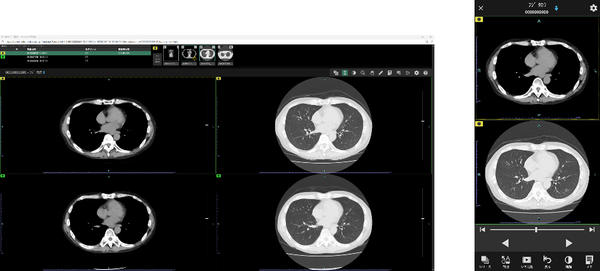

近年,CTやMRIなど画像診断機器の高度化により,医師が確認すべき画像枚数は増加している。「SYNAPASE LEAD Cloud」には,特定機能病院の7割以上で導入されている読影ビューワ「SYNAPSE SAI viewer」を標準ビューワとして採用した。「SYNAPSE SAI viewer」は高いカスタマイズ性を備えており,ユーザーの好みに応じて操作性や表示画面を柔軟に設定できる。画像配置を簡便に行える「レイアウティング機能」や,過去検査の画像と現在の画像を自動的に同期させる「自動スライス位置合わせ機能」など,多彩なワークフロー支援機能を搭載している。これにより,読影業務の効率化を図り,画像診断を強力にサポートする。

Cloud viewer (左:PC版,右:モバイル版)